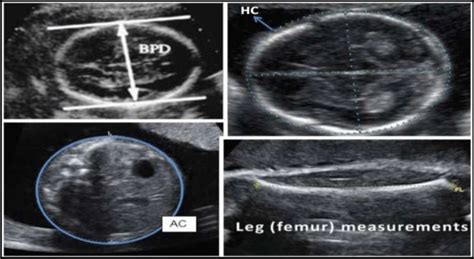

• BPD (Biparietal Diameter): This measurement refers to the distance across your baby’s head, from one side to the other. Think of it as the width of their head. It’s one of the earliest measurements taken during an ultrasound and helps estimate gestational age (how far along you are in your pregnancy) and assess head size. This measurement is crucial because it helps to monitor the baby’s head development and can give clues about potential complications. The BPD is measured in millimeters (mm). The BPD is especially important because it can help determine if the baby’s head is growing appropriately. If the BPD is too large or too small for the gestational age, it could indicate a variety of issues, such as macrosomia (large baby), microcephaly (small head), or other underlying conditions. However, a single measurement outside the normal range isn’t necessarily a cause for alarm. Your doctor will consider other factors and measurements to get a complete picture.

• HC (Head Circumference): As the name suggests, HC measures the circumference of your baby’s head. It’s essentially the measurement around their head. Similar to BPD, HC is used to assess head size and monitor growth. This measurement often gives a more complete picture of the head’s size than BPD alone, especially if the head shape isn’t perfectly round. The HC is a great overall indicator of the baby’s head development. Along with the BPD measurement, the HC measurement helps paint a comprehensive picture of your baby’s overall head development and can help pinpoint any abnormalities early on. Your doctor will use these measurements to ensure your baby’s head is growing at a healthy rate. Like all the measurements, the HC is expressed in millimeters (mm), and your doctor will compare the result to a range of normal values for your baby’s gestational age. The head circumference is another key indicator of the baby’s growth and development, and along with BPD, the HC is one of the more important measurements. It is important to know that all of these measurements are important and contribute to a thorough understanding of the baby’s health.

• AC (Abdominal Circumference): This measurement focuses on the circumference of your baby’s abdomen. It helps assess the size of their belly and can be an indicator of their weight and overall growth. This measurement is particularly useful in estimating the baby’s weight, which is important for planning the delivery. AC can be used to monitor the growth of the baby’s organs. The AC is used to assess the baby’s weight and overall growth. AC is measured in millimeters (mm). This measurement gives doctors an estimate of the baby’s weight, which helps them assess if the baby is growing well or if there are any potential issues. The AC is also important because it can give insight into the baby’s overall well-being. It is usually taken at the level of the baby’s stomach and is a key indicator of the baby’s overall size.

• FL (Femur Length): This measurement is the length of your baby’s femur, which is the thigh bone. It helps estimate the baby’s overall size and can be used in conjunction with other measurements to assess their growth. The FL measurement is used as a good indicator of the baby’s overall skeletal development and gives doctors a clue about the baby’s overall length. This measurement can also help estimate the baby’s weight. FL is measured in millimeters (mm). The femur length measurement can also help doctors estimate the baby’s overall size and assess whether the baby’s bones are developing as they should be. The femur length can be another sign for your doctor to check for potential developmental delays. The FL can also be used in combination with other measurements to estimate the baby’s weight and overall size, allowing your doctor to keep track of the baby’s growth.